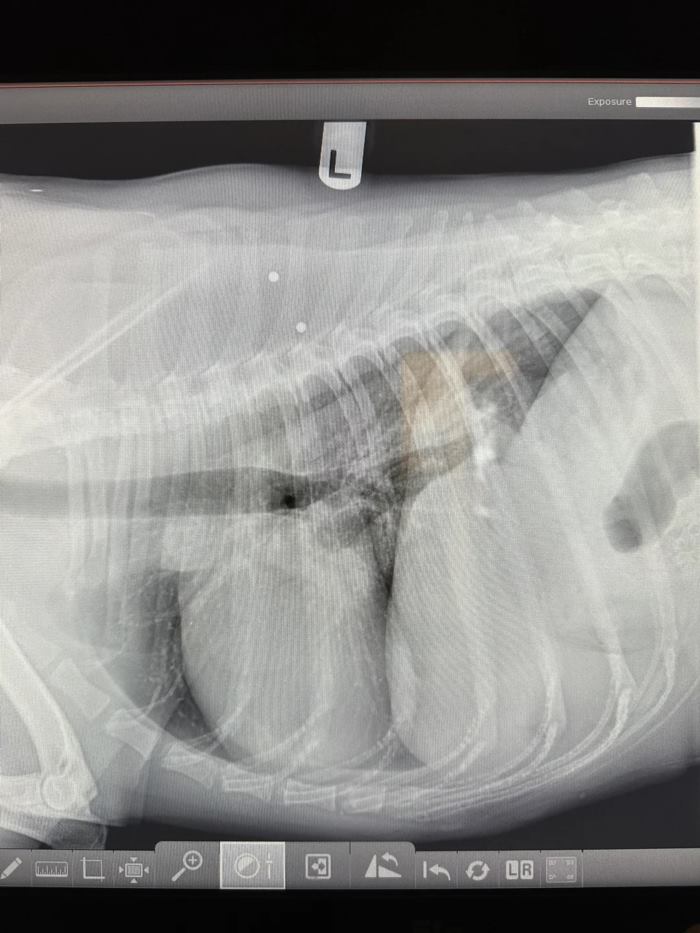

และไม่เคยสงสัยอะไร กระทั่งได้เห็นภาพเอกซเรย์ปรากฏออกมา

"กระสุนนัดหนึ่งอยู่ใกล้กระดูกสันหลังของมัน ฉันมั่นใจว่าถ้ามันไปโดนกระดูกสันหลัง มันคงส่งผลร้ายแรงมากกว่านี้" โบฟอร์ด กล่าว

โบฟอร์ด เผยว่า เขาไม่เคยเห็นเจ้าบีนส์แสดงออกว่ามีบางอย่างอยู่ในตัวมัน หรือแม้กระทั่งแสดงความเจ็บปวดให้เขาเห็น มีเพียงบางครั้งที่มันจะมีอาการผงะถอย หลังจากที่เขาเผลอไปสัมผัสตรงช่วงหลัง เขาไม่เคยคาดคิดมาก่อนมาว่าจะมีกระสุนฝังอยู่ในตัวมัน และยิ่งเมื่อนึกย้อนไปในตอนที่มันถูกยิงนั้น มันยังเป็นแค่สุนัขเด็ก ทำให้เขารู้สึกโกรธและเศร้าใจมาก